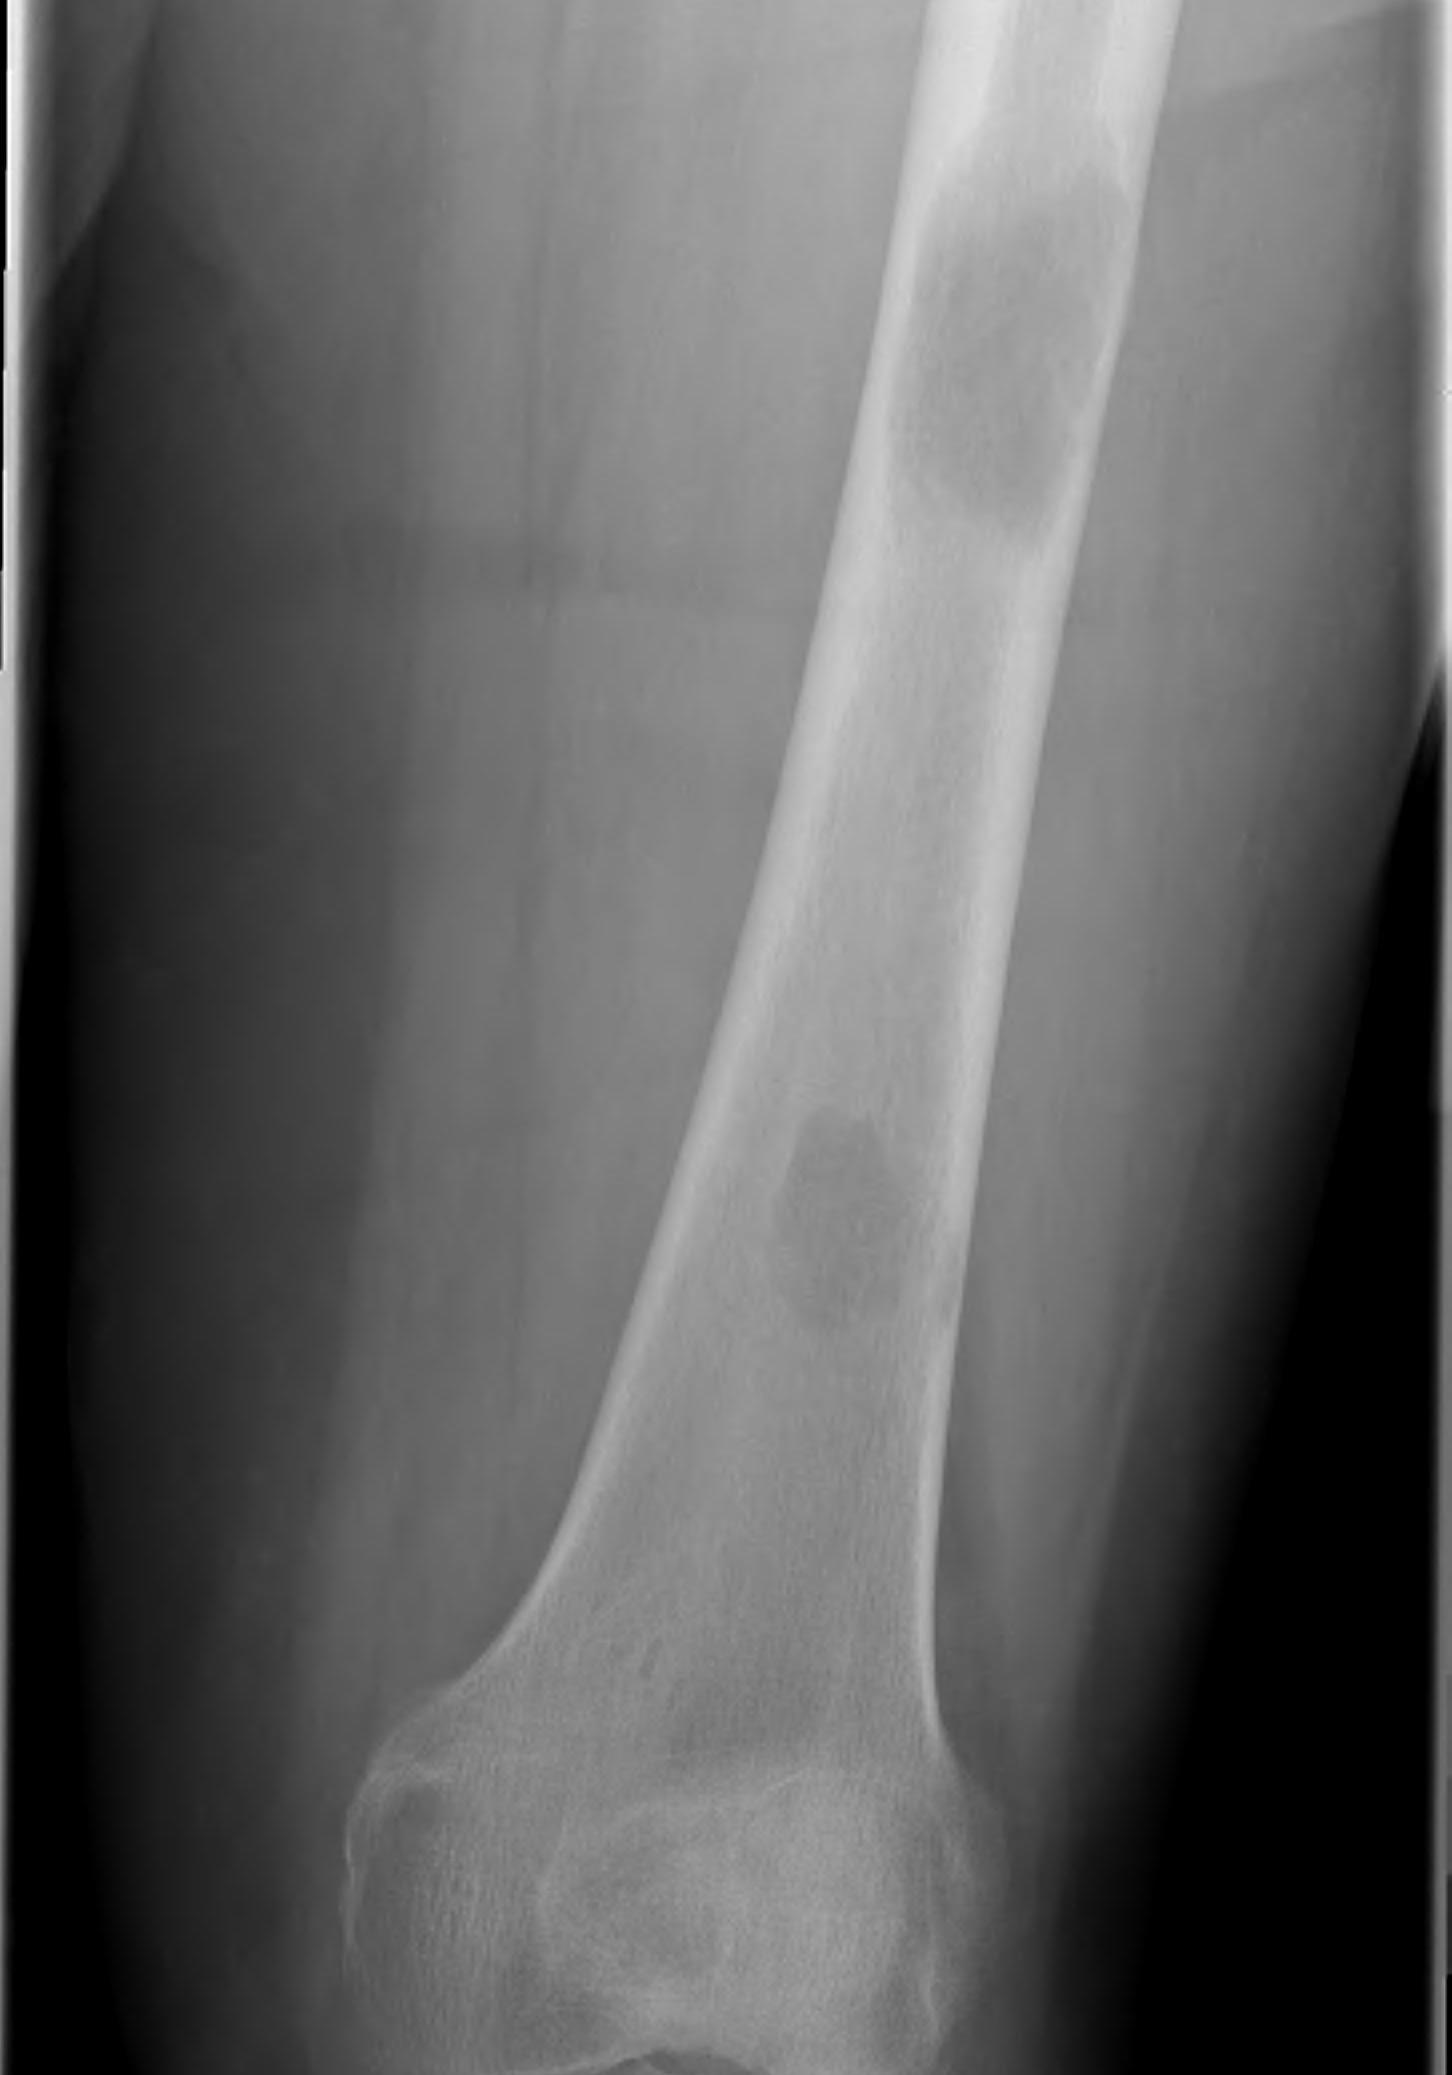

Tibia

Greenbaum et al Am J Orthop 2017

- 43 tibial metastasis

- proximal tibia most common

- variety of treatements

- plate / nail / arthroplasty